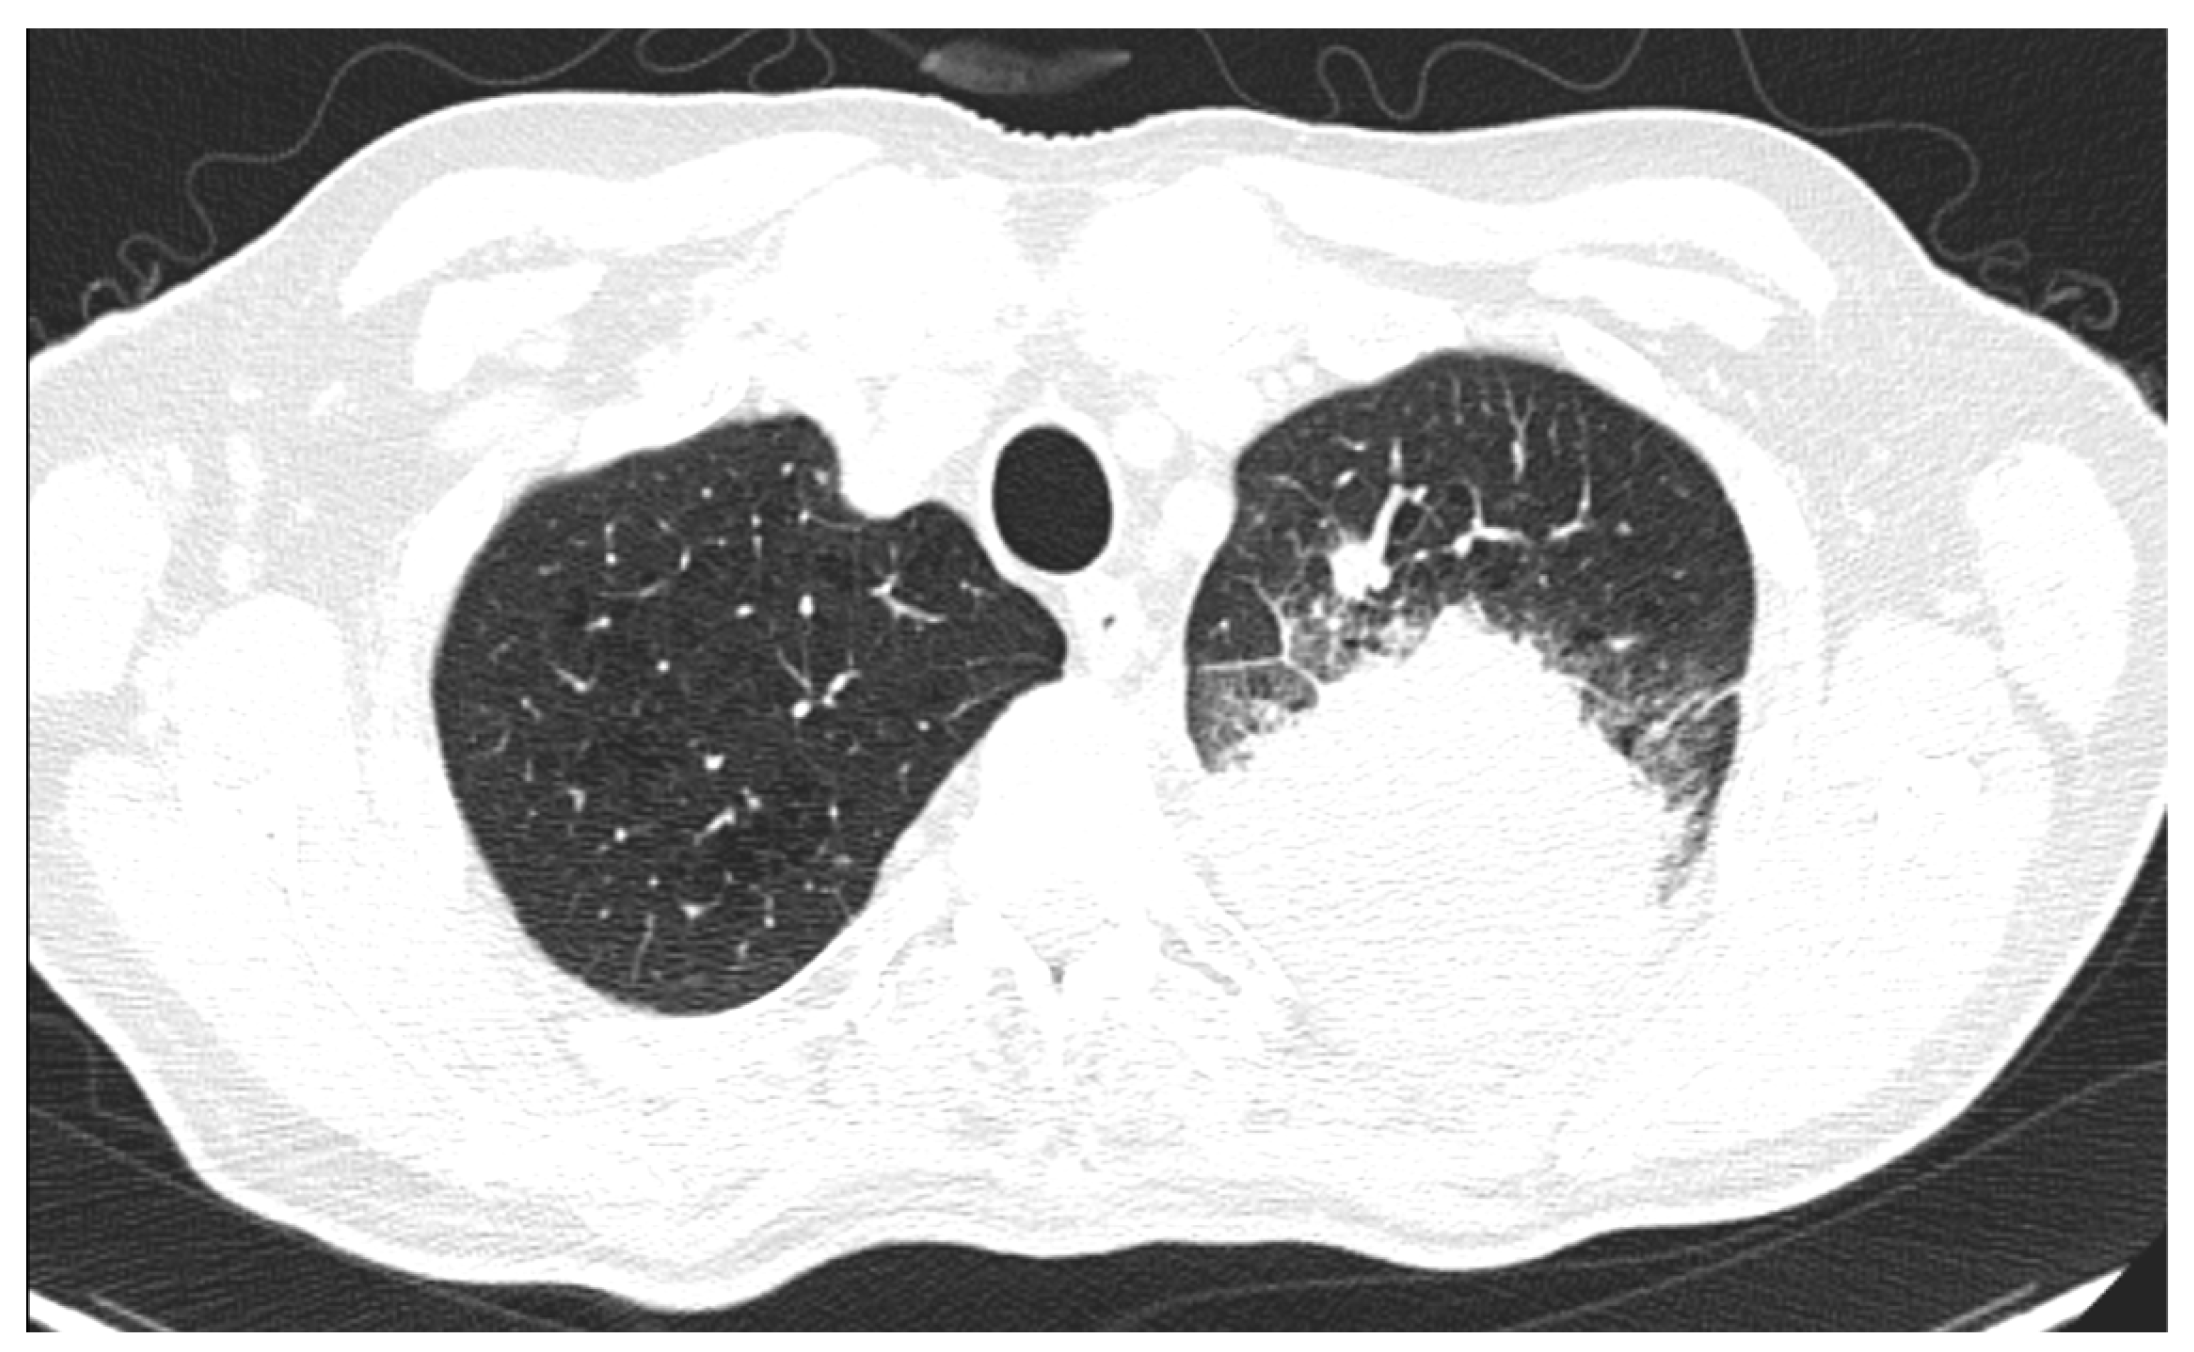

3.2.3. Tumoral Margins

3.2.4. Cavitation